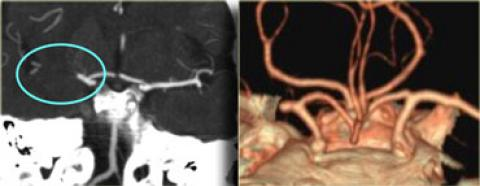

Hình ảnh tăng tỷ trọng động mạch não giữa MCA bên trái, do huyết khối hoặc tắc mạch. Tương ứng với tắc MCA trên CTA.

Hình ảnh tắc động mạch não giữa MCA bên phải trên CTA